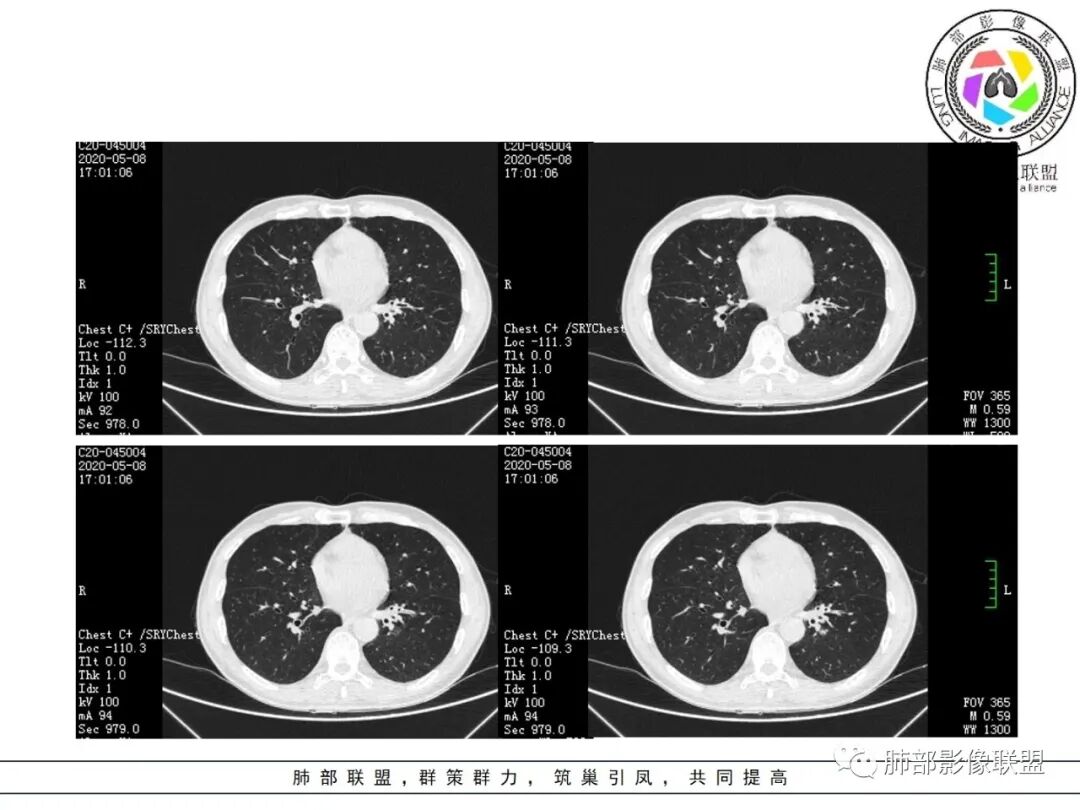

大雄:抗感染不吸收还是要警惕癌尤其主动脉旁的病灶红星:老年患者,咳嗽咳痰两个月,既往有糖尿病病史10年,左肺下叶后基底段斑片状、条索状、斑点状多形态的病灶,病灶内可见支气管征以及狭窄扩张的支气管影像。重建图像上可见到病灶沿支气管爬行。增强扫描病灶轻度强化,临近胸膜增厚。首先考虑感染性的病变,结核性的可能性最大。鉴别诊断上注意排除肺克以及淋巴瘤。三个石头:左肺下叶多发斑片,结节,条索,多态性?结核?多个结节边缘长毛刺,胸膜牵拉,分叶。矢状位支气管走行扭曲,没有完全阻塞,应该有粘液栓,有点像指状。主动脉旁病灶边缘平直,部分有鹏隆感,延迟强化。抗炎病灶变化不明显,结核?真菌?肿瘤也除外不了。没意见:左肺下叶基底段结节,膨隆、深分叶,毛刺,内侧串珠结节,中轴间质增厚,管腔狭窄,后基底段亚支不张,强化情况不明,考虑恶性,腺癌可能性大,另指套样征像,支气管壁增厚,不除外霉菌感染流心明智:老年患者,咳嗽咳痰2月。既往糖尿病史10年。胸CT:左肺下叶基底段多发结节影、斑片影、条索影,多数结节影沿支气管血管束分布,支气管壁厚,部分结节分叶、指状突,后基底段支气管狭窄闭塞。重建可见到病灶沿支气管爬行。增强扫描病灶明显强化,部分斑片影内可见低密度灶。普通抗感染无效。考虑:恶性病变,鳞?小?鉴别TB、隐球等。王秀仙:左肺下叶沿支气管血管束分布斑片、结节影,部分呈管状铸型生长,管腔狭窄,后基底段支气管阻塞,降主动脉旁不张实变,增强扫描病灶轻度强化,抗感染2周无吸收,考虑鳞癌。鉴别结核。蓝天白云:肺野内老年男性,咳嗽咳痰,有糖尿病病史,抗炎治疗无吸收。影像表现为左肺下叶支气管腔内结节影,支气管壁增厚,远侧小花小草,增强后实变影均匀强化,考虑鳞癌伴远端阻塞性炎症,鉴别结核。采莲:老年男性,咳嗽咳痰2月,有糖尿病史,左肺下叶沿支气管分布多发结节条状影,结节影不规则有分叶,成串珠样,靠下结节影成条索影,周围有空气储留,靠近主动脉不规则块状影,边缘平直,周围支气管壁增厚,支气管进入后阻塞,有糖尿病史,首选考虑炎性肺结核可能性大,鉴别肺鳞癌。了:左肺多发结节影,实性结节,,磨玻璃结节,左肺门结节影,深分叶,彭隆感,有血管滋养,考虑肿瘤,抗感染后病灶无吸收,感染不像,结节有强化,无卫星灶,结核可以排除不再涩的柠檬:老年男性,吸烟史,糖尿病史,咳嗽咳痰2月,抗感染2周无效。左下基底干及各分支管壁较弥漫增厚,伴支气管粘液栓,远端阻塞性肺炎,后基底段部分不张实变。先考虑感染病变,常规抗炎无效,需考虑结核、曲霉等,不能排除鳞癌合并感染,建议支气管镜检查。

尘缘:支气管壁增厚,沿支气管分布斑片状影,中远端支气管似堵塞,远端阻塞性改变,需要鉴别结核与肺癌,临床简单,镜检就行了。读片个人倾向于鳞癌伴感染吧。田园晚风:老年男性,有糖尿病史,咳嗽咳痰2月,左肺下叶沿支气管分布多发结节条状影,部分有分叶,成串珠样,靠下结节影成条索影,周围有空气储留,靠近主动脉不规则块状影,边缘平直,周围支气管壁增厚,支气管进入后阻塞,首选考虑肺癌可能性大,鉴别肺结核。

结节伴分叶。

2.关于支气管:上述病灶辖区外侧段支气管截断,环壁结节,远端阻塞性肺炎,是肺癌的重要征象。

3.关于胸膜增厚:本例未见明显的胸膜凹陷及牵拉。病灶较小价值收缩力不强,同时因鳞癌的破坏力强,也抵消了肿块本身的收缩力。

4.关于临床资料:老年男性,长期吸烟史,肺气肿背景,要警惕鳞癌的可能性。

5.关于阻塞性肺炎:同一部位反复发生的感染,治疗效果不佳或反复发生,应仔细搜寻相关气道异常,警惕肿瘤导致阻塞性肺炎的可能。